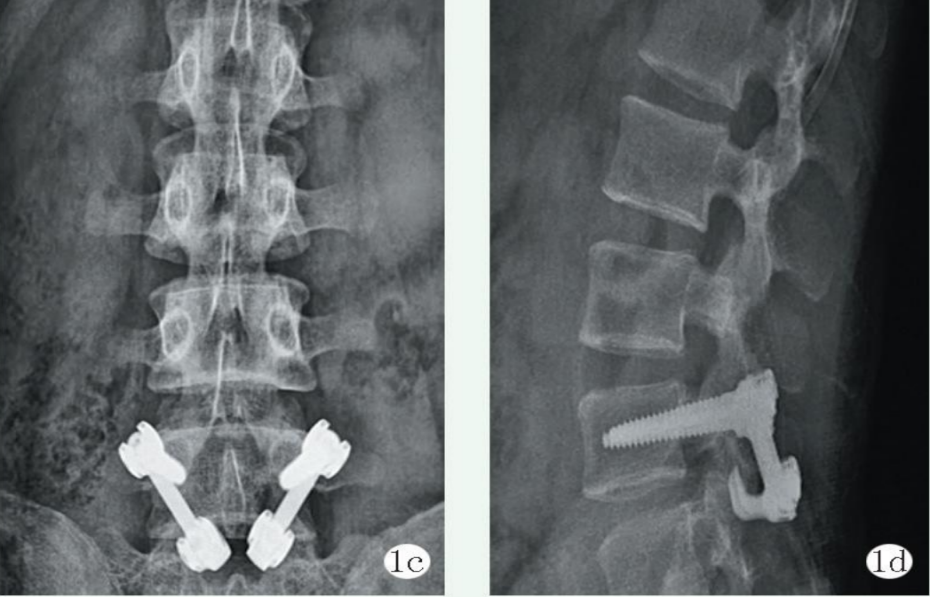

該技術(shù)由病椎打入椎弓根螺釘,然后在椎板下緣插入椎板鉤,清理峽部斷端并植骨后加壓椎板鉤并與椎弓根螺釘鎖定。

有文獻(xiàn)顯示,椎弓根釘-椎板鉤固定法在手術(shù)時(shí)間、術(shù)中出血、皮膚切口大小等方面,相較于節(jié)段間融合均具有顯著優(yōu)勢(shì);術(shù)后隨訪時(shí),椎弓根釘-椎板鉤固定法也能更快的緩解疼痛,并能更快恢復(fù)正常生活。

L4/L5椎弓根釘聯(lián)合V形棒內(nèi)固定;

L5/S1椎弓根螺釘內(nèi)固定